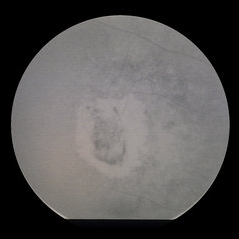

Proliferative Diabetic Retinopathy with Subhyaloid Hemorrhage

Oct 18 2012 by Suber S. Huang, MD, MBA, FASRS

43-year-old diabetic man with proliferative diabetic retinopahty, subhyaloid hemorrhage, ischemia, neovascuarization.

Photographer: Stacie Hrvatin

Condition/keywords: ischemia, retinal neovascularization, subhyaloid hemorrhage